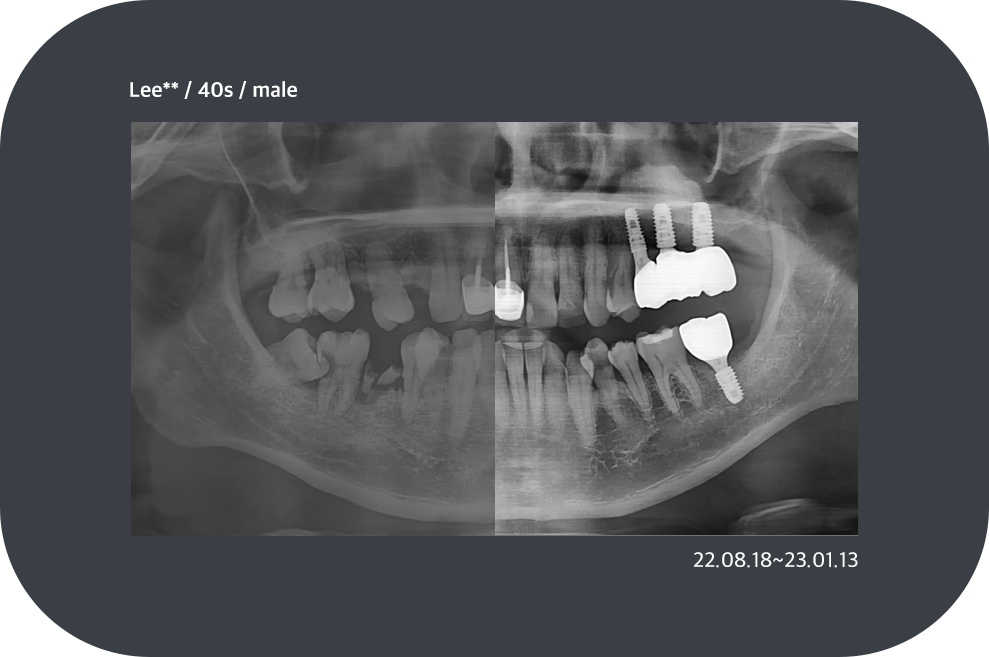

치료사례

임플란트 치료사례

implant_case01

implant_case02

implant_case03

implant_case04

*모든 증례 사진은 의료법 제23조, 제56조에 의거하여, 당사자의 동의하에 게시하였습니다.

*치료 사진은 모두 본원에서 치료한 환자분의 사진입니다.

*치료 사진은 모두 동일인의 사진이며, 동일조건에서 촬영하였습니다.

*개인의 차이에 따라 시술 및 수술 후 부작용이 발생할 수 있으며, 의료진과 충분한 상담을 받으시기 바랍니다.